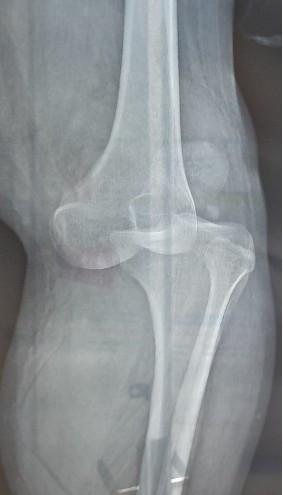

Phẫu thuật thành công trường hợp bị trật khớp gối, đứt động mạch khoeo sau tai nạn ảnh 1Hình ảnh tổn thương chân trái của anh Thái Văn H. Ảnh: TTXVN phát

Bác sỹ Chuyên khoa I Nguyễn Phú Nhứt, Khoa Ngoại tổng hợp, Bệnh viện Đa khoa tỉnh Bạc Liêu thông tin, ngày 18/9, anh H. nhập viện trong tình trạng sưng, đau, hạn chế khi vận động khớp gối trái sau tai nạn giao thông.

Theo người nhà anh H, trước đó 2 giờ, anh H chạy xe máy tự ngã. Lúc vào viện, anh H. tỉnh táo, sưng nề, bầm tím, biến dạng gối trái, cẳng bàn chân trái tím, lạnh, mất mạch chày trước chày sau chân trái.

Ngay lập tức, anh H được sơ cứu, siêu âm mạch máu, chụp CTA chi dưới khẩn cấp và được chẩn đoán đứt động mạch khoeo trái trên gối/trật khớp gối trái do tai nạn giao thông. Sau đó, ê-kip các bác sỹ Khoa Ngoại tổng hợp và Khoa Chấn thương chỉnh hình phối hợp tiến hành phẫu thuật khẩn cấp ngay cho bệnh nhân.

Anh H đã được các bác sỹ nắn trật khớp gối, cố định khớp gối bằng đinh Kisner, mở cân cẳng chân giúp giảm chèn ép khoang, bộc lộ động mạch khoeo trên và dưới gối. Bệnh nhân được phục hồi động mạch khoeo bằng tĩnh mạch hiển tự thân đảo ngược đầu, khâu phục hồi tĩnh mạch khoeo... và đang được tiếp tục điều trị kháng sinh, giảm đau. Sau 5 ngày phẫu thuật thành công, chân trái của anh H đã hồng ấm, mạch rõ, vận động cảm giác bàn chân trái tốt.

Bác sỹ Chuyên khoa I Nguyễn Phú Nhứt cho biết thêm, trường hợp tổn thương mạch máu phối hợp khá thường gặp của trật khớp gối với tỷ lệ từ 7 - 40%, tỷ lệ cắt cụt chi là khoảng 10%, tỷ lệ cắt cụt sau phẫu thuật là khoảng 5%. Đây là một trong những phẫu thuật khó do vị trí đứt khó tiếp cận để phục hồi mạch máu. Thời gian vàng để cứu chi là khoảng 6 giờ; nếu không được chẩn đoán và phẫu thuật kịp thời dễ dẫn đến cắt cụt chi. Vì vậy, để phẫu thuật thành công, cần phải có sự phối hợp nhanh chóng, chính xác, nhịp nhàng từ các khoa cấp cứu, khoa chẩn đoán hình ảnh, khoa gây mê và ê-kip bác sỹ phẫu thuật.